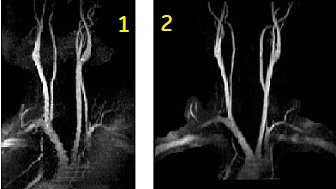

Use gated 2D Fast TOF to acquire popliteal and carotid artery images

| 1 | Standard, non-gated TOF |

| 2 | Gated TOF |

- to reduce artifacts due to pulsatile flow and to acquire aortic bifurcation and iliac images